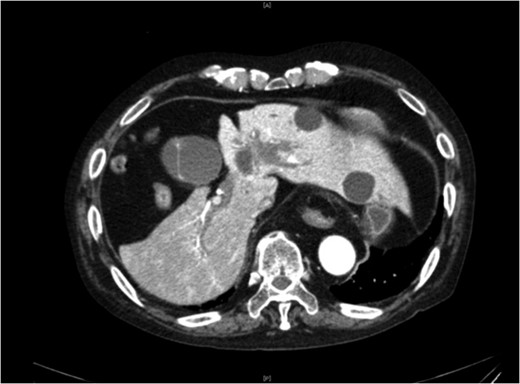

The patient’s vital signs were normal, with no fever, and the pain was diffuse, with no tenderness. Hematological findings showed mild inflammation (WBC 10 700/μl, CRP 1.07 mg/dl) and elevation of hepatobiliary enzyme (AST 69 U/l, ALT 370 U/l, LDH 228 U/l, ALP 982 U/l, γ-GTP 518 U/l), but no jaundice was observed (T-Bil 0.9 mg/dl). Abdominal ultrasonography revealed gallbladder distention, but no gallstones, fluid surrounding the gallbladder, gallbladder wall thickening or sonographic Murphy’s sign were observed. Abdominal contrast-enhanced CT revealed extravasation of contrast medium in the gallbladder, and the patient was diagnosed with gallbladder bleeding (Fig. 1).

Abdominal contrast-enhanced CT. Abdominal contrast-enhanced CT revealed extravasation of contrast medium in the gallbladder.